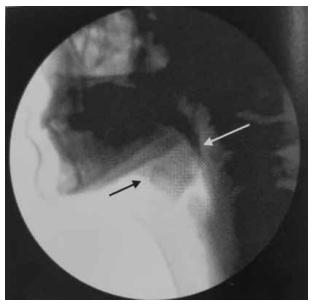

Observe, a seguir, a imagem de uma videofluoroscopia.

(Magalhães e Magnoni, Disfagia orofaríngea no adulto e no ambiente hospitalar)

Assinale a alternativa que corretamente a caracteriza.